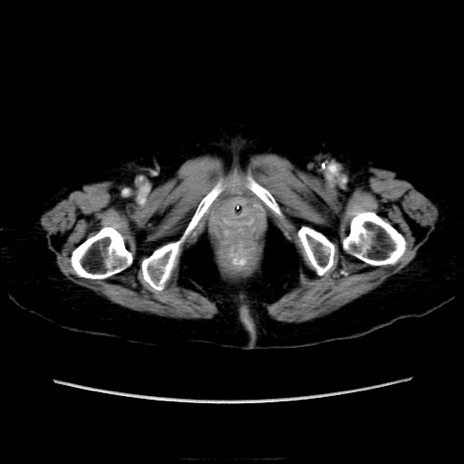

症例40(横断像)

【症例】90歳代女性

【主訴】腹痛・嘔吐

【現病歴】 食欲低下、嘔吐があり昨日他院受診。肺炎と診断され入院となる。入院後より腹部全体に圧痛あり。胃管留置され経過みていたが、症状持続するため、

当院転院となる。

【既往歴】胸椎圧迫骨折、胆石症

【身体所見】腹部:中央に激痛あり、圧痛あり、反跳痛不明

【データ】WBC 17100、CRP 18.82

横断像